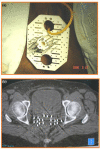

Figures